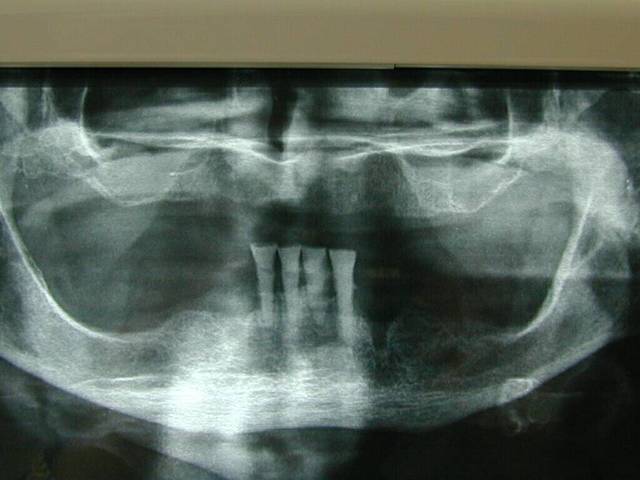

Tu veux des diskimplants, tu auras des diskimplants. Voila un cas fait il y a 5 ou 6 ans, avec de l'os trés mou (du D3 devant c'est pas courant)

Me suis trompé le cas date de 98, et la pano a 2 ans.

Pour curieux impécunieux s'abstenir, les 35 et 45 répondent aux critères définissant l'ostéointégration, désolé! Quant à "pas d'os en mésial", le truc ovale noir que tu vois sous l'implant, c'est un machin que l'on appelle le trou mentonnier, t'inquiètes pas.

Panacher pourquoi pas: tu as un appui trabéculaire et cortical. Maintenant tu en auras certains qui sont pour et d'autres contre: il y a plusieurs théories de la basale.

l'ostéointégration mésiale 35 et 45 est inexistante , pas d'os en mésial ? Quelle est le pronostique pour ces deux implants ?

On voit bien en effet la confirmation bi-latérale sur la periapicale